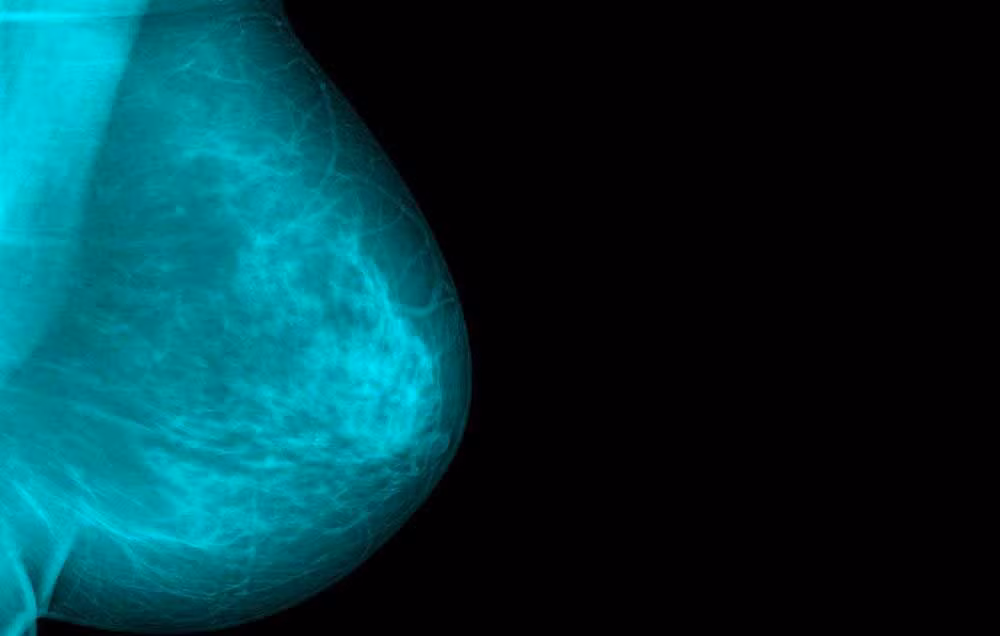

(Kiến Thức) - Nổi bướu không phải là dấu hiệu ung thư vú duy nhất mặc dù phổ biến nhất. Phụ nữ cần chú ý đến những dấu hiệu không điển hình khác để phát hiện ung thư sớm.

Rất nhiều phụ nữ bị ung thư vú chia sẻ kinh nghiệm rất phổ biến là họ cảm thấy vùng ngực nổi một khối cứng mà trước đó không có rồi sau đó khối này chuyển thành ung thư. Một nghiên cứu sơ bộ tại Anh cho thấy cứ 6 phụ nữ ung thư vú thì có 1 bệnh nhân có triệu chứng không phải là nổi bướu. Chính những dấu hiệu ung thư vú không điển hình này sẽ ảnh hưởng đến việc điều trị vì trong ung thư, càng phát hiện và điều trị sớm càng tốt.